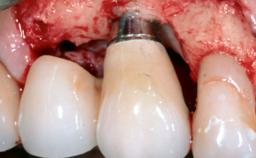

Late Presentation of Peri-Implant Mucositis Requiring Soft-Tissue Augmentation and Esthetic Crown Lengthening at Implant Site 11